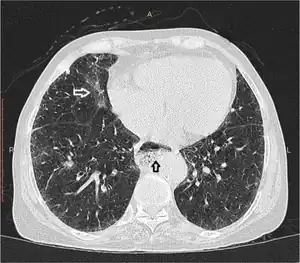

| Esophageal dysmotility black arrow | |